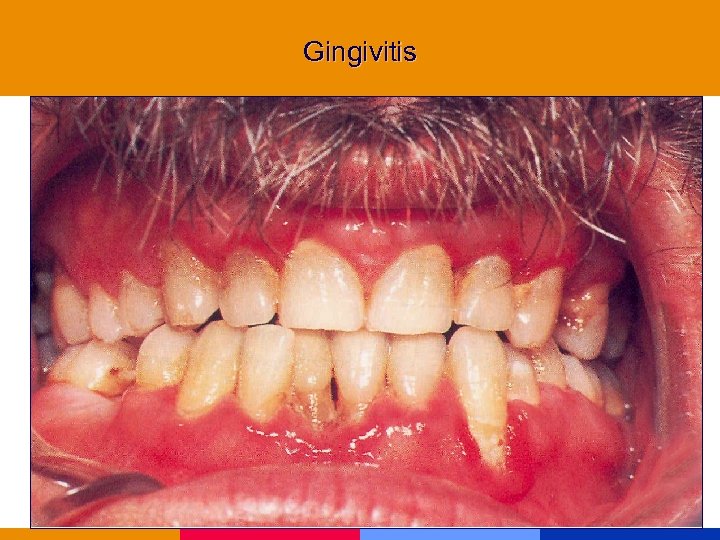

Gingivitis

Gingivitis

Gingivitis

Gingivitis